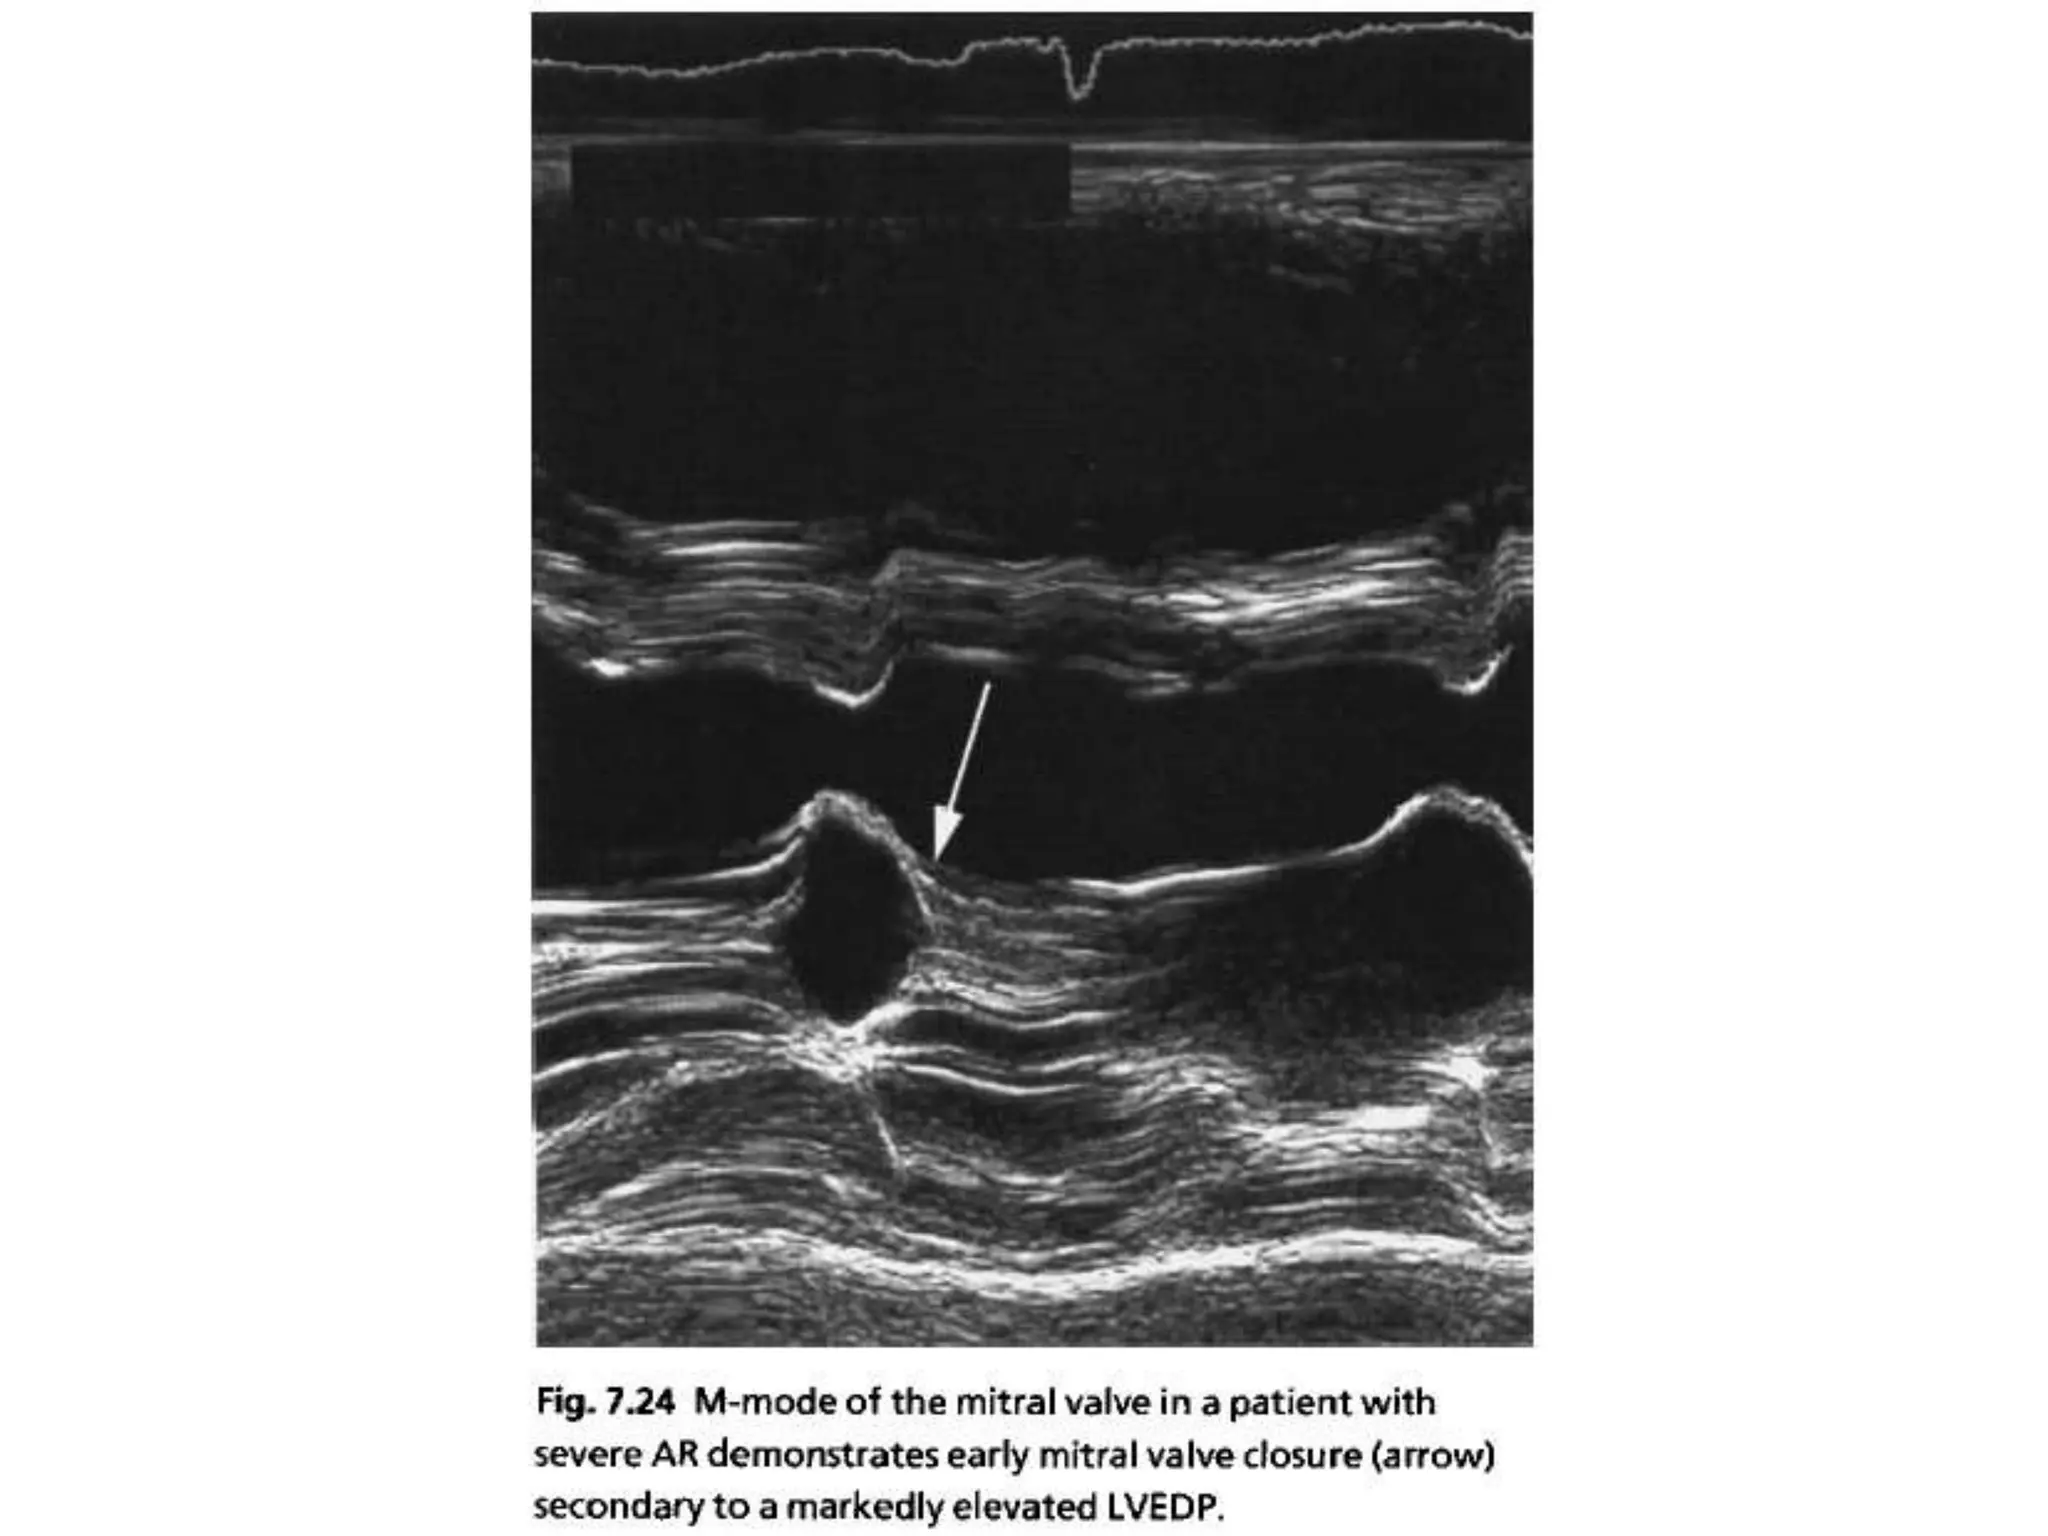

• Shape of the envelope CW doppler

• Premature mitral valve closure

ACUTE VS CHRONIC • Shape of the envelope CW doppler • Rate of deceleration of flow • Premature mitral valve closure • Endocarditis,dissection • Normal lv dimensions